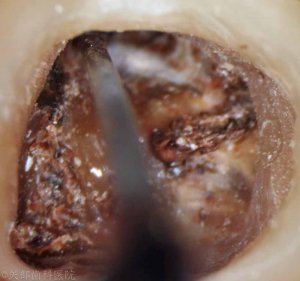

細菌の侵入と汚染によって根管内部はボロボロの状態でした。

根管周囲の象牙質にも細菌の侵入が認められ真っ黒になった象牙質がボロボロと取れていきます。

健康な象牙質が薄くなり被せものをかぶせた後に咬合力で歯根破折を起こしてしまう可能性があります。